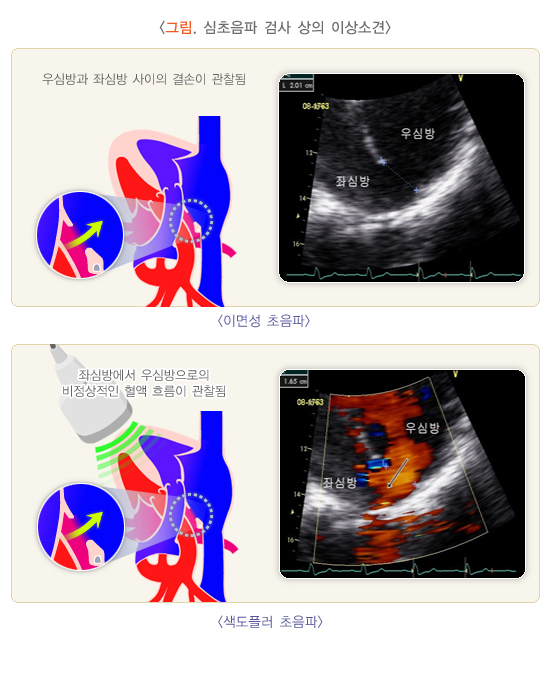

1. 이면성(2 dimensional; 2D) 심초음파

부채꼴 모양으로 초음파를 발사한 다음, 여러 부위에서 돌아오는 초음파의 강도를 점(dot)들로 배열하여 실시간으로 이면성 평면 영상을 얻는 기법을 말합니다. 심방과 심실, 혈관의 크기와 기능, 판막의 형태학적인 평가를 할 수 있습니다.

3) 색 도플러(Color flow mapping)

혈류의 방향, 속도에 따라서 색으로 표시되는 영상